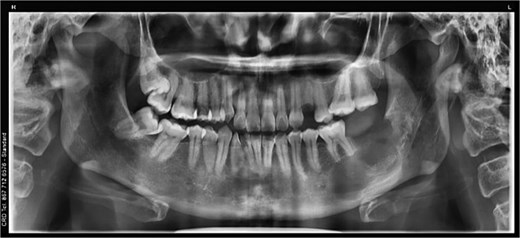

A 43-year-old female with no significant medical history was referred following the incidental radiographic detection of a unilocular radiolucent lesion in the left mandibular angle associated with a horizontally impacted third molar. Clinical examination revealed no pain, inflammation, or neurosensory alterations. Panoramic imaging (Fig. 1A) and cone-beam computed tomography demonstrated a well-defined lesion at the cemento-enamel junction, with cortical thinning, buccolingual expansion, inferior alveolar canal displacement, and root resorption of adjacent molars (Fig. 1B). The differential diagnosis included unicystic ameloblastoma and odontogenic keratocyst.

Preoperative imaging studies. (A) Panoramic radiograph. (B) Cone beam computed tomography.